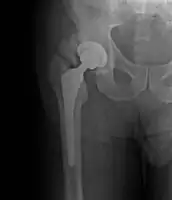

- Locations

- Hip most common - typically after ORIF (52% any grade, 19% Grade III-IV) or THA (43% any grade, 9% Grade III-IV)

Classification

Brooker Classification: (radiographic)

- I - islands of bone within the soft tissue (clinically silent)

- II - bone spurs from the pelvis or proximal femur; >= 1 cm gap between opposing surfaces (clinically insignificant)

- III - bone spurs from the pelvis or proximal femur; < 1 cm gap between opposing surfaces (clinically significant)

- IV - ankylosis (clinically significant)